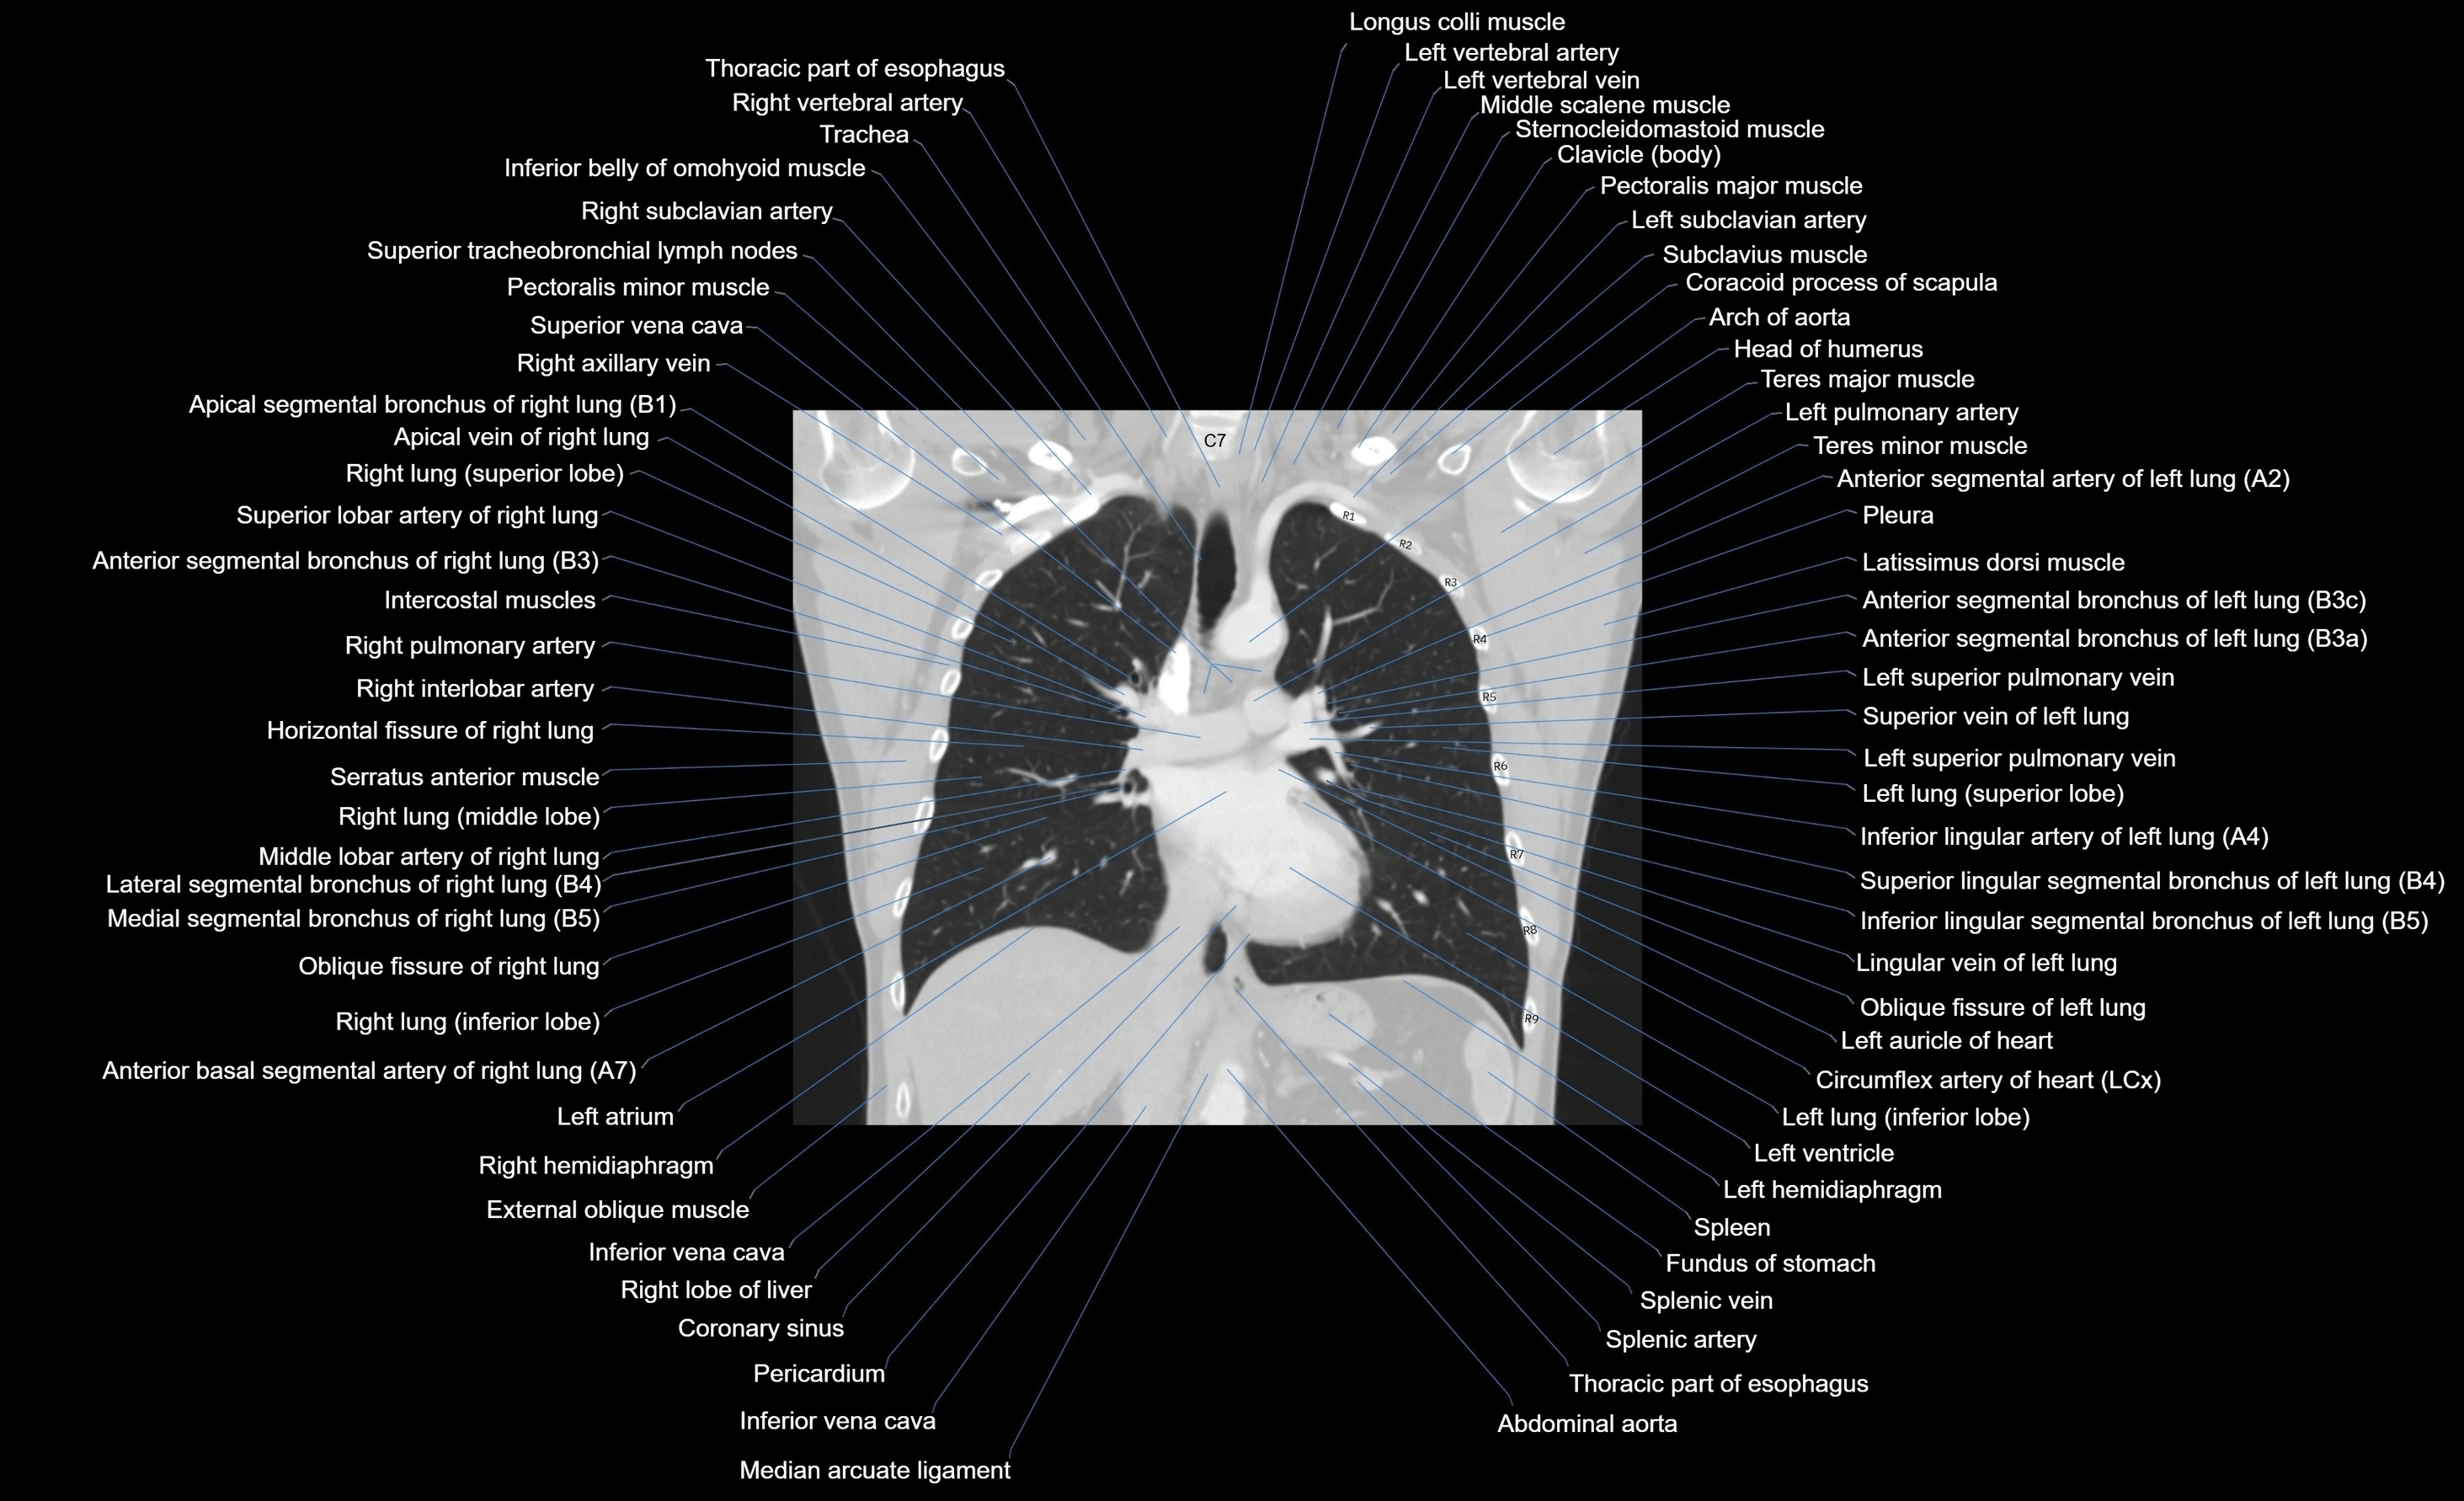

- Arch of aorta

- Brachial plexus

- Coracoid process of scapula

- Descending thoracic aorta

- Head of humerus

- Horizontal fissure of right lung

- Latissimus dorsi muscle

- Left Lung (Superior Lobe)

- Left brachiocephalic vein

- Left common carotid artery

- Left hemidiaphragm

- Left lung (inferior lobe)

- Left pulmonary artery

- Left ventricle

- Median arcuate ligament

- Middle lobe of right lung

- Oblique fissure of left lung

- Oblique fissure of right lung

- Pectoralis major muscle

- Right lobe of liver

- Right lung

- Right lung (inferior lobe)

- Right lung (middle lobe)

- Right lung (superior lobe)

- Right pulmonary artery

- Spleen

- Splenic artery

- Splenic vein

- Subclavius muscle

- Subscapularis muscle

- Superior vena cava

- Supraspinatus muscle

- Teres major muscle

- Teres minor muscle

- Thoracic part of esophagus

- Trachea